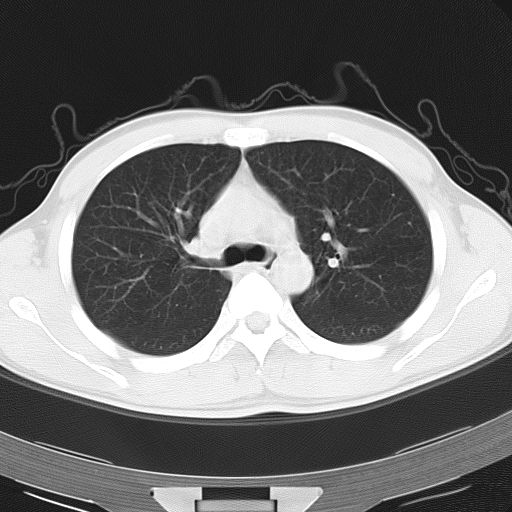

男,34岁,咳嗽2~3个月,无咳血,病初有发热。

病变分布以双上肺叶外带明显,双下肺未见异常,此一点不十分支持肺泡蛋白质沉着症,病变未见铺碎路石征,也不肺泡蛋白质沉着症。考虑间质性肺炎,结核不除外。

肺泡蛋白沉积症;胸膜下区磨玻璃样,实变区见纹理走形,地图样改变。做mri。

ct表现 (1)中央型:表现为蝶翼状浸润性阴影对称分布于两侧肺门周围,其内可见支气管充气征,病变区与正常肺组织分界清楚。(2)外围型:表现为多发性条片状、斑片状及斑块状高密度影,弥散、对称或不对称分布于两肺或一侧肺外围部位。病变区与正常肺组织及脏层胸膜面分界清晰,呈地图样改变。hrct可显示小叶间隔增厚及肺小叶内淡淡的密度增高影等细微结构,同时易发现肺大疱、肺气囊及节段性肺不张。

再仔细阅读该病人的ct片,我们不难发现,病例所表现的正是外围型的肺泡蛋白沉积症表现,即:为多发性条片状、斑片状及斑块状高密度影,弥散、对称或不对称分布于两肺或一侧肺外围部位。病变区与正常肺组织及脏层胸膜面分界清晰,呈地图样改变。

该病人经过1周抗炎治疗,病灶基本消退,仅存毛玻璃样改变。